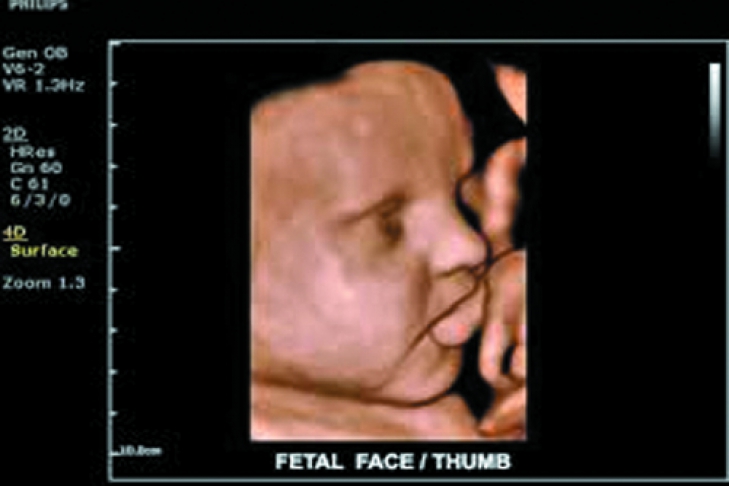

В США состоялась презентация новой ультразвуковой системы ClearVue 650 от Royal Philips. Уникальная технология Auto Face Reveal, используемая в данной системе, дает возможность не только точно определить дату зачатия, распознать движения плода на 2 недели раньше, чем обычно, выявить нарушения его сердечной деятельности на ранних стадиях. ClearVue 650 позволит увидеть лицо малыша, находящегося в утробе.

Вообще спектр применения новой ультразвуковой системы очень широк. Новинку можно использовать в урологии, акушерстве и гинекологии, исследований молочных желез, сердечно-сосудистой и костно-мышечной систем. В системе реализована возможность четырехмерной визуализации (4D), что делает диагностику более точной и качественной.